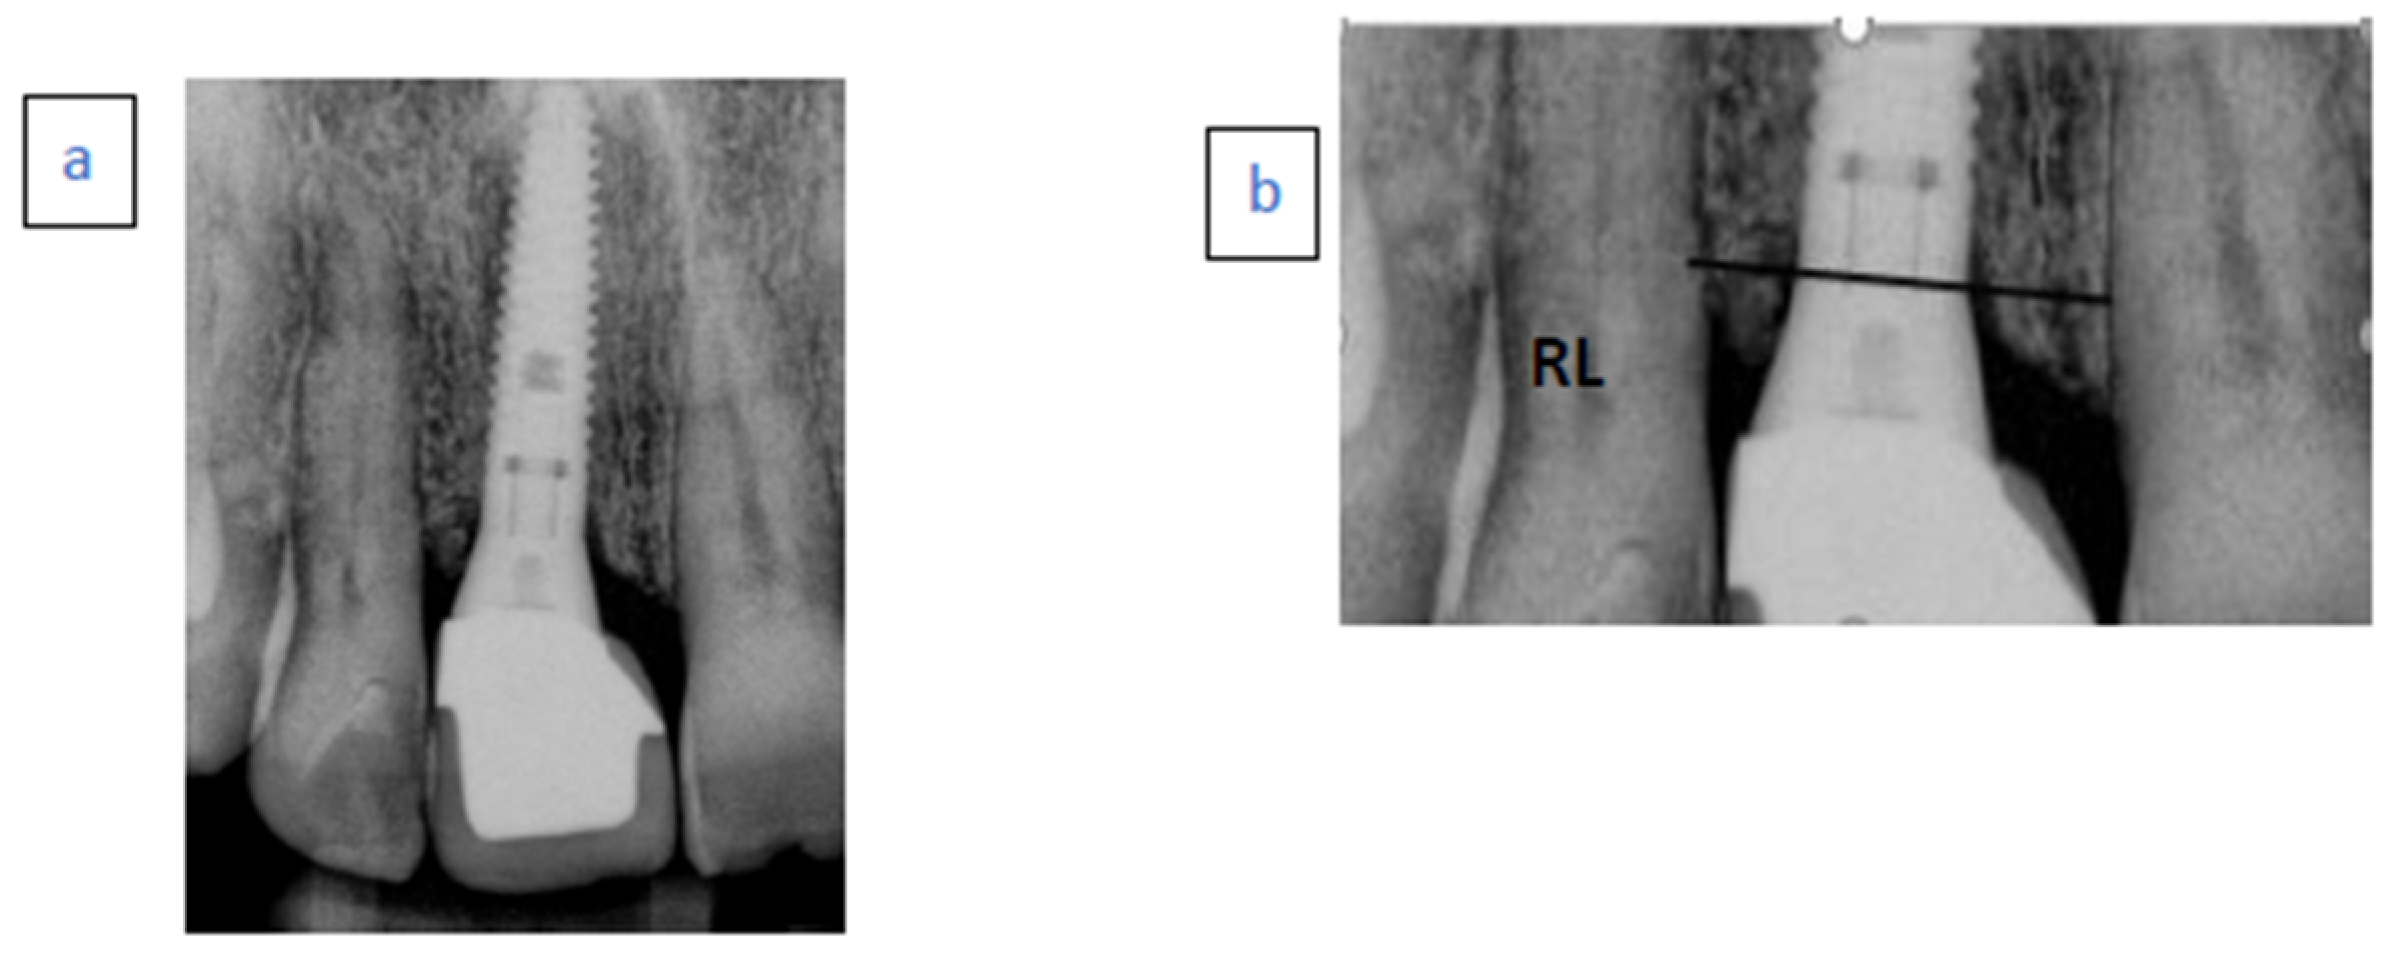

- Case 3 (a) Hopeless left central incisor due to advanced bone loss.

- Case 3 (b) Immediate implant placement with temporary abutment. Radiopaque material demonstrated above the implant neck.

- Case 3 (c) Follow-up examination after 96 months.